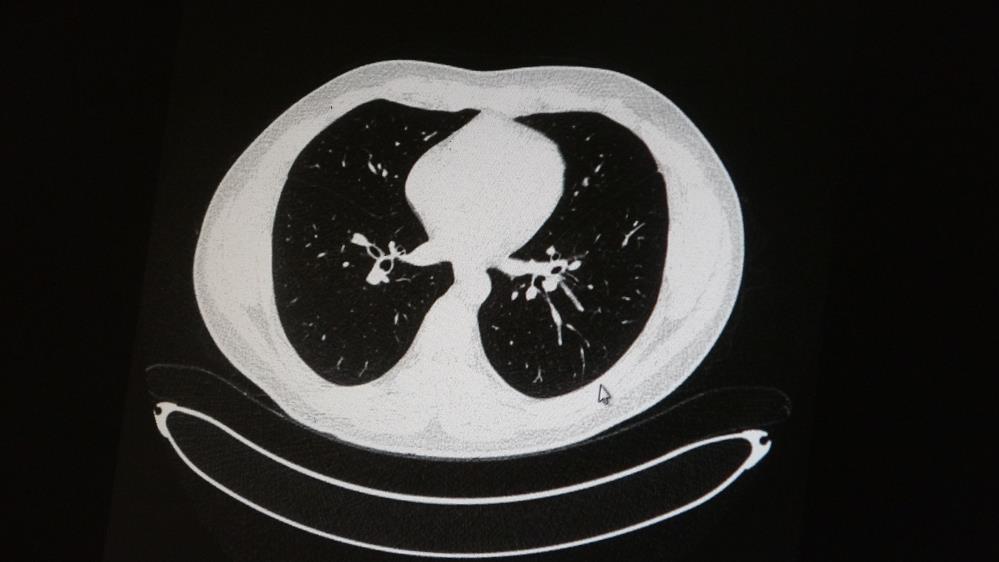

Uzm. Dr. Azar, aynı şekilde aşı olup koronavirüs hastalığına yakalanan bir başka genç hastanın akciğer tomografisinde akciğerde herhangi bir sorunun olmadığını ve hastanın durumunun iyi olduğunu gözlemlediklerini kaydetti.

AŞI OLAN HASTANIN AKCİĞER TOMOGRAFİSİ: